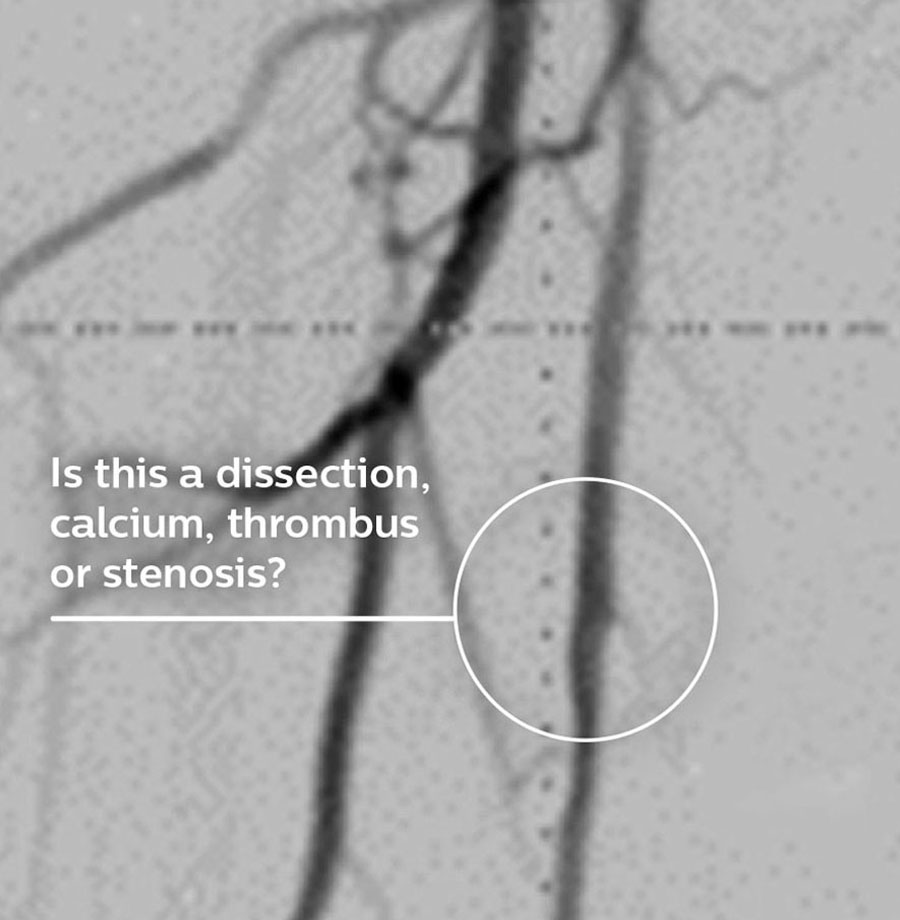

Eine Angiographie liefert Informationen über die luminalen Eigenschaften peripherer Arterien, unterbewertet aber das Ausmaß der Atherosklerose bei Patienten mit peripherer arterieller Verschlusskrankheit (pAVK) erheblich, selbst bei „normal erscheinenden“ Gefäßen.1

Dr. Stavroulakis erörtert, wie der Schweregrad einer pAVK durch eine reine Angiographie häufig unterschätzt wird und wie mithilfe von IVUS der prozentuale Stenosegrad und die Plaque-Belastung präzise gemessen und quantifiziert werden können.